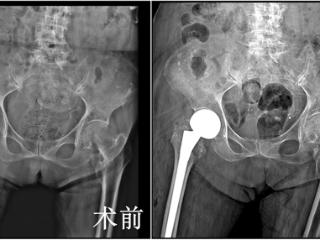

西安市红会医院MDT救助101岁股骨粗隆间骨折老人